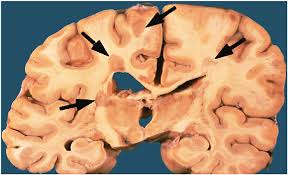

Ένα άλλο διακριτό χαρακτηριστικό της νόσου είναι η ατροφία του φλοιού . Στην ουσία , το εξωτερικό στρώμα του εγκεφάλου σταδιακά συρρικνώνεται και μέσω MRI αυτή η ανατομική φθορά μπορεί να είναι ορατή . Παράλληλα , ορατές είναι και συγκεκριμένες περιοχές που ονομάζονται πλάκες . Στις περιοχές αυτές συσσωρεύονται τα “τραυματισμένα ” κύτταρα που προκύπτουν λόγω αυτοανοσίας , και δημιουργούν μια διακριτή μάζα .

εγκέφαλος με πολλαπλή σκλήρυνση

Pape, A., Wellman, L. L., & Conran, R. M. (2022). Educational Case: Multiple sclerosis. Academic Pathology, 9(1), 100036. https://doi.org/10.1016/j.acpath.2022.100036